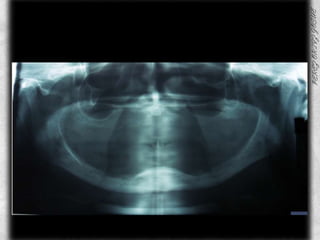

PRESENTA RUIDOS ARTICULARES, LLAMADOS CHASQUIDOS, SIN PRESENCIA DE CREPITACIONESSOBREPESOANODONCIA TOTAL  POR MUTILACIONES MULTIPLES CANDIDA ALBYCANS

ANALISIS INTRAORAL